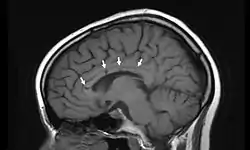

![]() مقطع سهمي بالرنين المغناطيسي النووي لدماغ امرأة عمرها 19 سنة مصابة بمتلازمة سوساك، تظهر فيه ثقوب صغيرة (احتشاءات دقيقة) في وسط الجسم الثفني، وهي علامات وَاصِمَة لمتلازمة سوساك مقطع سهمي بالرنين المغناطيسي النووي لدماغ امرأة عمرها 19 سنة مصابة بمتلازمة سوساك، تظهر فيه ثقوب صغيرة (احتشاءات دقيقة) في وسط الجسم الثفني، وهي علامات وَاصِمَة لمتلازمة سوساك | |

المظهر في الأشعة: في تحليل حديث (سوساك وآل 2003) تم مراجعة صور الرنين المغناطيسي من 15 مريضا يستوفون المعايير التشخيصية لمتلازمة سوساك. كان هناك إصابات عديدة البؤر فوق خيموية توجد في العديد من المرضى. معظم الإصابات كانت صغيرو (3 إلى 7 مم) إلا أن بعضها كان أكبر من 7 مم. كان كل المرضى مصابين بإصابات في الجسم الثفني مع منظر مثقوب للخارج عند متابعة صورة الرنين المغناطيسي. على الرغم أن المادة البيضاء هي أكثر الأجزاء إصابة إلا أن تركيبات المادة الرمادية العميقة قد تصاب أيضا في العديد من المرضى (9 من 15) بالإضافة إلى السحايا الرقيقة (9 من 15) والتصلب اللويحي والالتهاب الدماغي النخاعي المنتشر الحاد وقد تشبه تغيرات الرنين المغناطيسي الموجودة في متلازمة سوساك.

ومع ذلك فإن الإصابات الثفنية في متلازمة سوساك توجد بشكل مركزي. وبالمقارنة، فإن المرضى المصابين بالتصلب اللويحي والالتهاب الدماغي النخاعي المنتشر الحاد يملكون إصابات في السطح السفلي من الجسم الثفني. تحدث إصابة المادة الرمادية العميقة بشكل شائع في الالتهاب الدماغي النخاعي المنتشر الحاد إلا أنها نادرة جدا في التصلب اللويحي. لاتحدث إصابات للسحايا الرقيقة بشكل قياسي في التصلب اللويحي أو الالتهاب الدماغي النخاعي المنتشر الحاد.